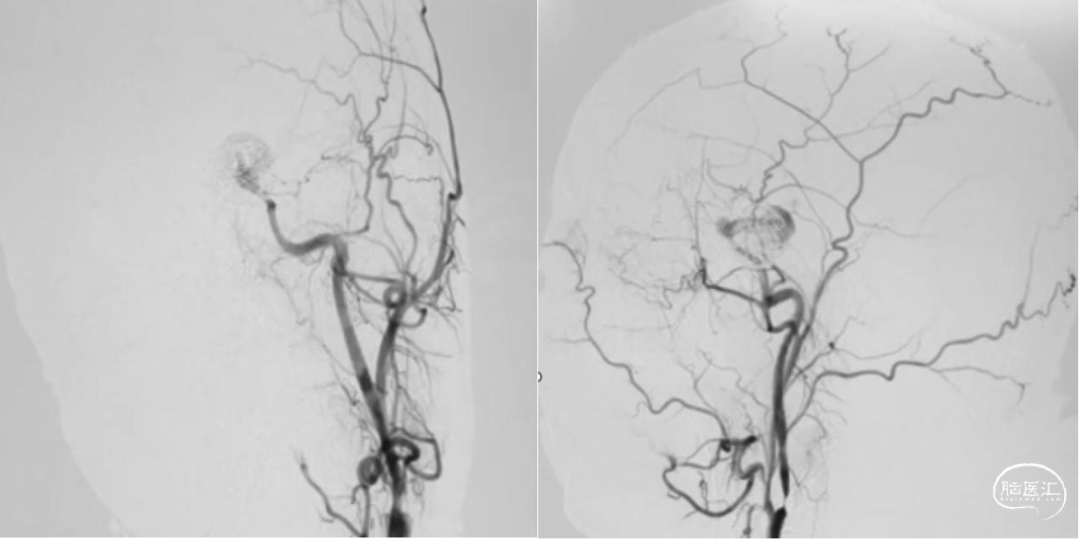

颈内动脉狭窄状况及闭塞试验

1. 术后一周复查DSA显示动脉瘤无血流,桥血管通畅。

2. 术后三个月复查CTA显示动脉瘤无血流,桥血管通畅。